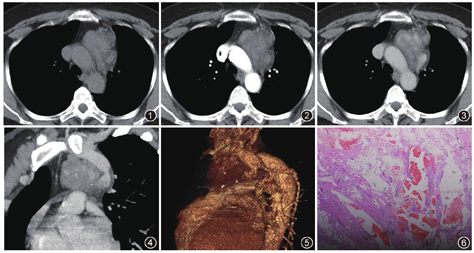

胸部CT平扫及增强扫描:左前纵隔自左侧头臂静脉下缘至主肺动脉水平可见一分叶状软组织密度肿块(图1),边界清晰,大小约6.4 cm×4.1 cm,增强动脉期局部轻度强化(图2),平衡期病变中心部分不均匀持续性强化(图3),边缘局部与头臂静脉间可见多条异常血管通路(图4),病变内可见多个点状钙化影(图5),肿块右缘紧贴主动脉弓,但无浸润,左缘突向肺内伴纵隔胸膜增厚。前纵隔病变CT考虑血管畸形。

手术所见:肿物位于升主动脉和主动脉弓左前方,约为9.0 cm×7.0 cm×4.5 cm,上端位于左侧头臂静脉后方,下端位于左侧肺门前方,灰白色有蓝色囊腔,呈囊实性,边界欠清,与左侧前上纵隔胸膜粘连,肿瘤上端有血管与左侧头臂静脉相连,后端与半奇静脉相连,左侧膈神经和迷走神经走行于肿瘤之中。离断上述2根血管,剖开肿瘤,游离出左侧膈神经和迷走神经,完整切除肿瘤。术后病理表现为大量不规则扩张血管结构,管壁平滑肌厚薄不均且排列不规则,部分管腔内见红细胞(图6)。诊断为前纵隔静脉性血管瘤。

纵隔静脉性血管瘤多为类圆形或分叶状软组织肿块,边界清晰,瘤内静脉石为本病特征性表现,但仅少数病例可见,且CT显示更敏感;增强扫描纵隔血管瘤多数为不强化或轻度不均匀强化的乏血供病变,病理基础为瘤内血管壁厚或管腔内血栓致管腔狭窄[2];而McAdams等[5]报道纵隔血管瘤的强化特点为中心性明显强化的富血供病变,其强化程度与对比剂推注方法和扫描时间有关。本病例CT平扫表现与典型静脉性血管瘤一致,而中心部分不均匀持续性强化符合富血供纵隔血管瘤,且头臂静脉与病变间可见多条异常通路,提示病变与静脉系统关系密切,影像诊断应考虑前纵隔静脉性血管瘤。